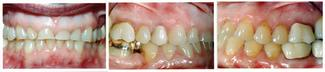

The composite buildups were completed twice during the orthodontic phase as the teeth were intruded (Figure 2). After a thorough discussion of her restorative choices, the patient chose porcelain-fused-to-metal crowns because of her heavy daytime clenching habit. The metal linguals allowed for minimal tooth reduction and preservation of the remaining mandibular enamel. She did not want to cosmetically whiten her teeth, and chose to postpone restorative treatment of her mandibular teeth.